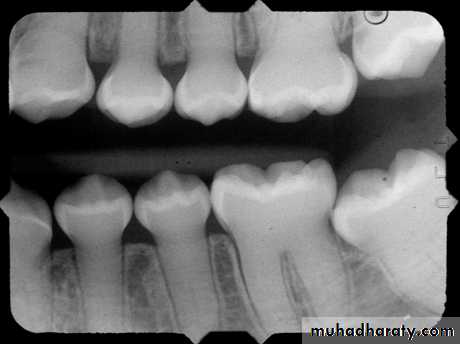

2. Fusion: two teeth fused with two pulps3. Gemination: wide crown with one pulp

FusionFusion of two tooth germs during

Proliferation stage

Geminationan attempted division of a single tooth germ by invagination occurring during the